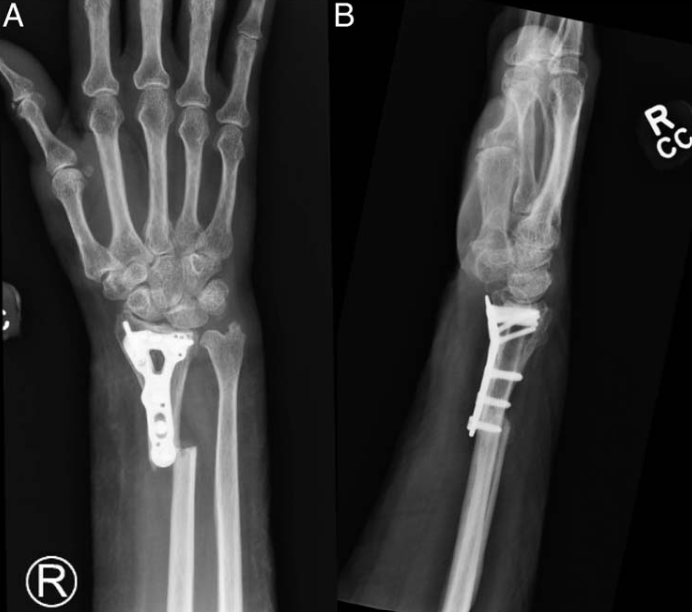

除临时固定外,单纯采用骑缝钉固定外踝骨折,也可避免钢板螺钉的内植物刺激,且在骨折愈合率上不存在劣势:

【1】Yoshimoto K, Noguchi M, Koseki T, Tominaga A, Okazaki K. Comparative effectiveness of nitinol staple-only fixation versus antiglide plate fixation for Weber type B distal fibular fractures. BMC Musculoskelet Disord. 2025 Jun 7;26(1):572.